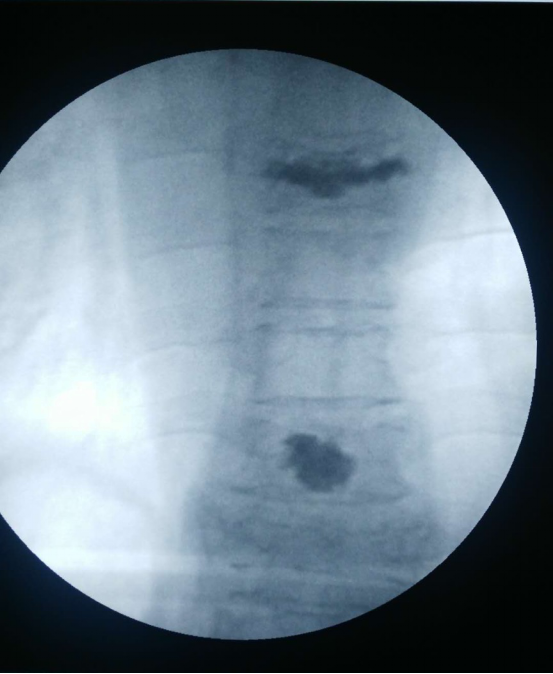

经过细致完备的术前准备,在局麻下为该患者实施了经皮穿刺椎体压缩骨折后凸成型术,在G型臂X光机透视定位目标T7、10椎体,用穿刺针在透视下穿刺入椎体,应用球囊缓慢撑开T7、10椎体,应用专用器械在监测下注入骨水泥T7约5ml,T10约3ml,透视见注入的骨水泥位置、形态良好,术毕,患者安返病房。患者随即感疼痛明显缓解,翻身自如。

术 后